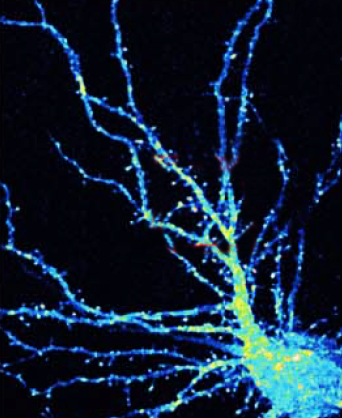

The new discovery shows how OPHN1 is involved in the trafficking of AMPARs, an essential feature of plasticity in neurons. Neurons move receptors away from synapses into their interior and then back to the surface of synapses to control connection strength. At the synaptic surface, receptors provide an opportunity for the docking of neurotransmitters, in this case glutamate molecules. After a cell has fired, surface receptors are typically brought back into the interior, where they are recycled for future use.

Van Aelst’s new experiments explain how OPHN1 in complex with another protein called Homer1b/c should normally interact with an area called the endocytic zone (EZ) to provide a pool of AMPARs to be brought to the synapse at a location called the post-synaptic density (PSD). When OPHN1 is mutated, the pool does not form and receptors needed for strengthening synapses are not available. Long-term potentiation is impaired.